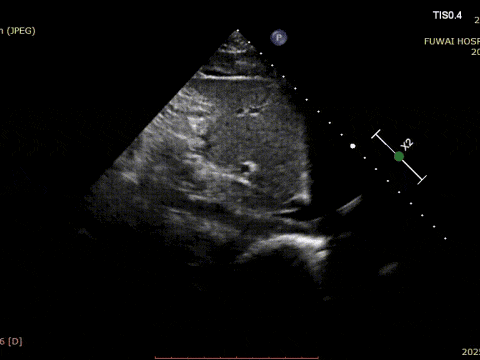

1. ASD był centralny w lokalizacji, ze zmierzoną średnicą około 8,1mm (widok bicaval) i 8,2mm (widok z krótkiej osi aorty).

Procedura była prowadzona przez TTE zgodnie z procedurą PAN opracowaną w szpitalu Fuwai. Ta bezpromieniowa technika obrazowania w czasie rzeczywistym oferuje wizualizację anatomiczną w wysokiej rozdzielczości, zapewniając dokładne umieszczenie urządzenia i minimalizując komplikacje-szczególnie cenne u młodych pacjentów w wieku rozrodczym.